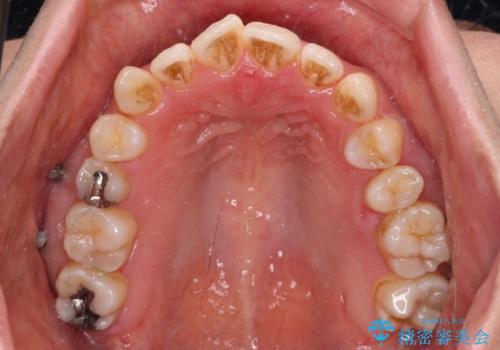

左上奥歯には乳歯が残存しており、後続永久歯は舌側に転位していました。

また、舌の突出癖の影響で上下前歯が接触していないオープンバイトとなっており、奥歯に負担のかかる咬み合わせとなっていました。

乳歯を抜歯し、舌側の永久歯を引っ張り出すこととしましたが、希望のインビザラインでは移動量が大きすぎて対応できない可能性があったため、ワイヤー装置にて改善することとしました。

ワイヤー装置にてある程度歯列が改善されたところで、上下をインビザラインにて矯正治療を行うこととしました。